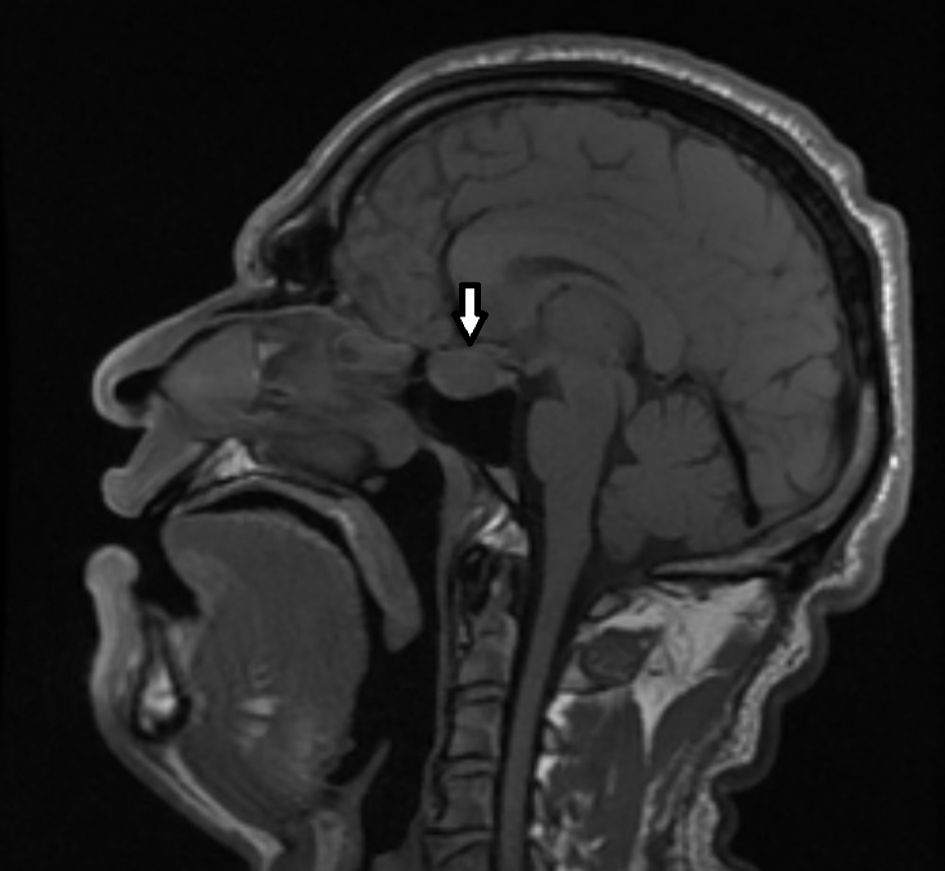

Magnetic resonance imaging (MRI) of the brain was performed with a focus on the hypothalamic-pituitary region in three planes, pre- and post-contrast examination with gadolinium enhancement. An advanced extra-axial, supratentorial focal lesion with markedly expansive growth and maximum dimensions of 21 × 13 mm, localized intra-, supra-, and parasellar bilaterally, with a predominance to the left was found. The formation presented with a complex structure and relatively homogeneous intralesional characteristic - hypointensity in T1. The described pathological “mass” was irregularly rounded, with smooth and sharp contours, and in its development demonstrated aggressive biological behavior. It exteriorized suprasellarly, compressing the optic chiasm, optic nerves and tracts, and chiasmal cistern. Laterally to the left, it involved the walls of the cavernous sinus and reached the walls of the carotid siphon. After application of contrast medium (CM), it retained its hypointensity. Occlusive ventriculomegaly was absent. Focal lesions in the brain parenchyma were not visualized, nor were intra-axial tumor formations supra- or infratentorially. Ventricular system, basal cisterns, and subarachnoid spaces along the convexity were normal for age. The finding corresponded to a pituitary macroadenoma (Fig. 2).

Click for large image

Figure 2. MRI of the brain showing tumor process in the sella turcica with signs of pituitary macroadenoma (sagittal plane). The arrow indicates the tumor mass. MRI: magnetic resonance imaging.